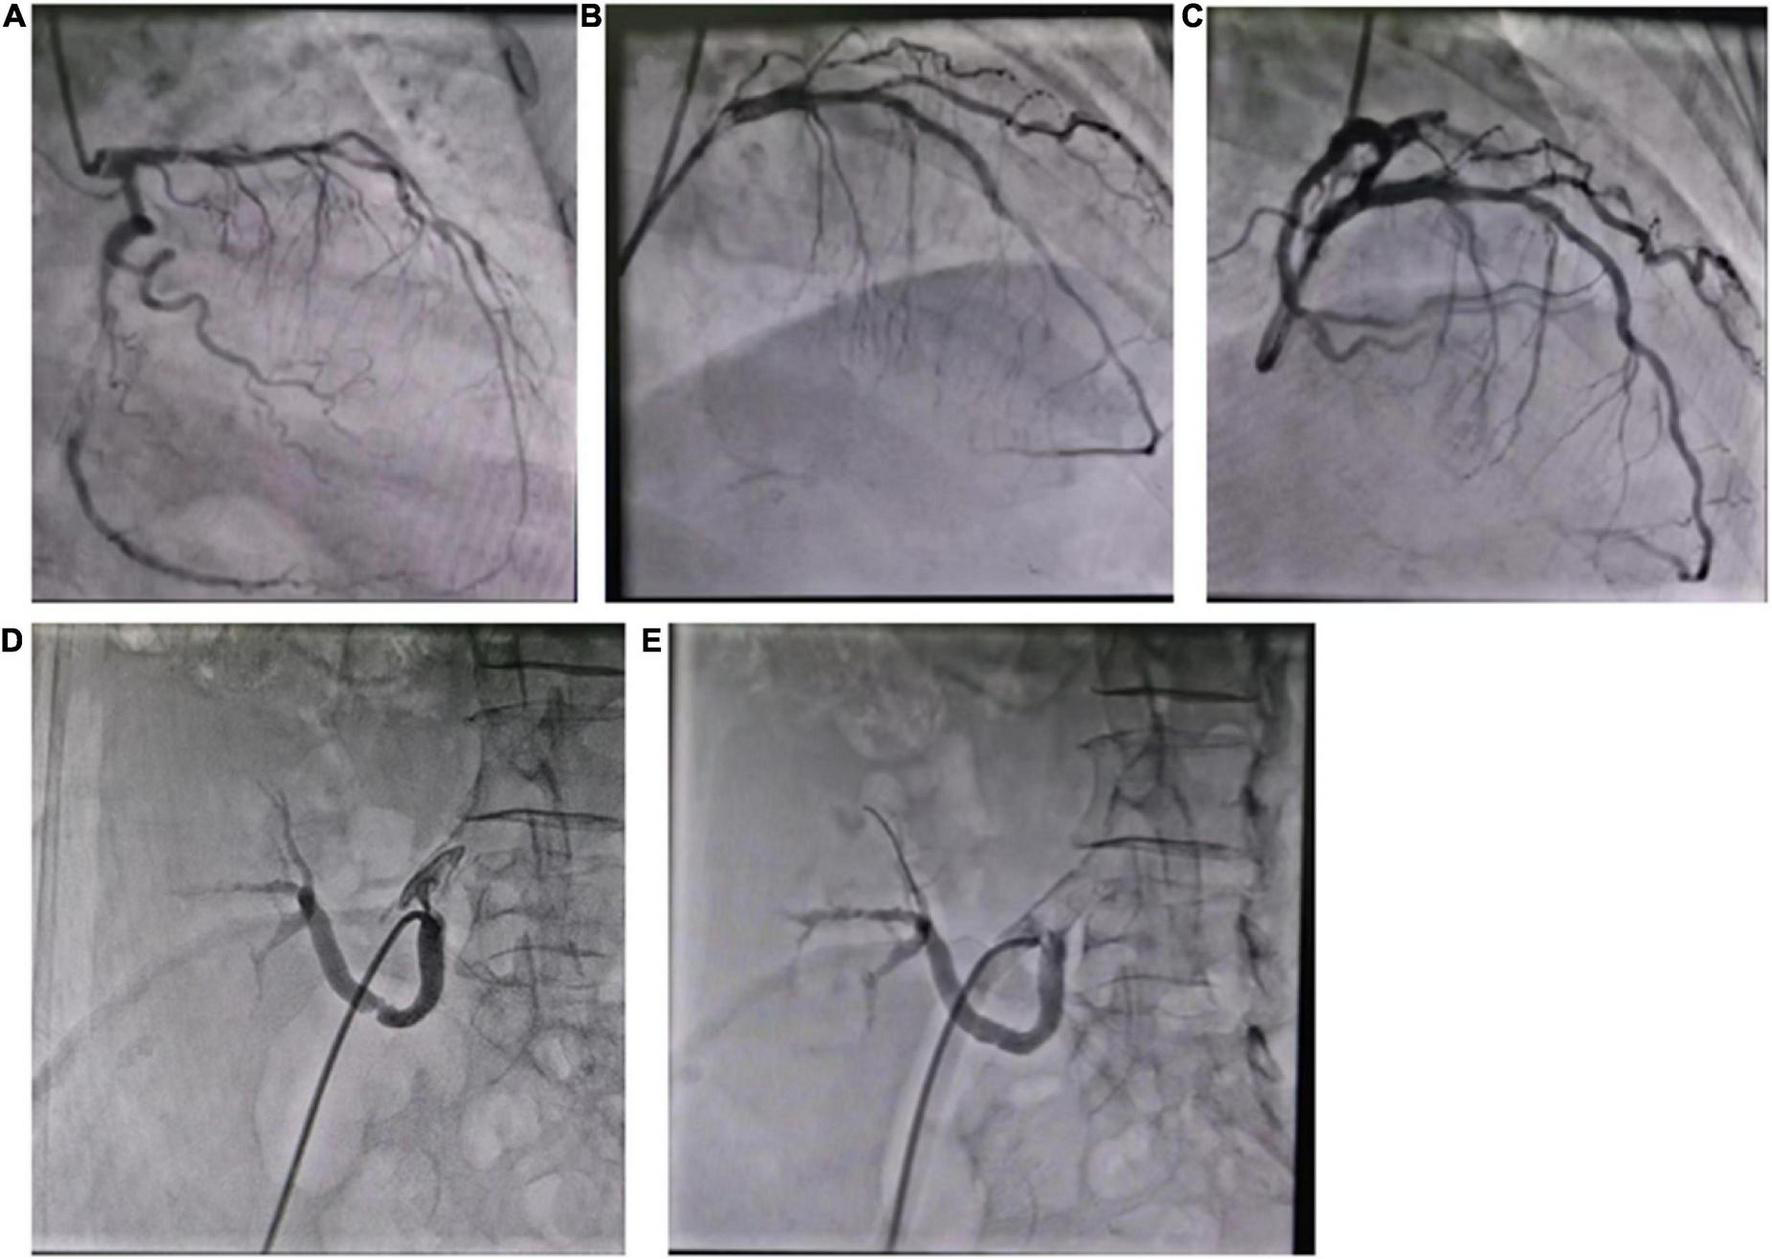

The patient developed exertional chest tightness 6 months earlier, which was progressively worsening with resting angina and the symptoms of heart failure of paroxysmal nocturnal dyspnea, lower extremity edema, and oliguria 1 month earlier. Her edema was relieved after the symptomatic treatment of diuresis, coronary vasodilatation, and albumin infusion in other hospitals. The physical examination showed stable vitals, mild anemia appearance, no jugular irritation, normal regular heart rhythm and normal heart sounds, and bilateral lower extremity edema; the rest of her examination was unremarkable. Laboratory results showed white blood cell (WBC) 4.60 × 109/L, hemoglobin 73 g/L, platelet 225 × 109/L, erythrocyte sedimentation rate (ESR) 52 mm/h, hypersensitive C-reactive protein (hs-CRP) 2.02 mg/L, normal liver enzymes, albumin 32.0 g/L, serum creatinine (Scr) 165.75 mmol/L, estimate glomerular filtration rate (eGFR) 30 ml/min/1.73 m2, K+ 4.37 mmol/L, creatine kinase (CK) 102 IU/L, creatine kinase isoenzyme (CK-MB) 1.4 ng/ml, troponin I (cTnI) 0.617 ng/ml, BNP 2841 pg/ml, total cholesterol (TC) 9.15 mmol/L, low-density lipoprotein (LDL-C) 6.22 mmol/L, positive for HBsAg, HBeAg and HBeAb, HBV-DNA 987000.00 IU/ml, thyroid stimulating hormone (TSH) 12.51 uIU/ml, normal HbA1C, and blood concentration of cyclosporine A 156.50 ng/ml. The electrocardiogram (ECG) showed reduced R wave and T wave inversion in inferior and anteroseptal leads. Ultrasonic echocardiogram showed segmental left ventricular (LV) wall motion abnormalities (LV apex, interventricular septum), left atrial enlargement, thickening of the left ventricular wall and interventricular septal base, LVEF 52.7%, mitral valve (after leaves roots) calcification, mitral and aortic valve mild reflux, aortic sclerosis/calcification, and a small amount of pericardial effusion (Figure 1). Coronary angiography after the improvement of heart failure showed triple-vessel disease (proximal left anterior descending artery (LAD) 90% stenosis, middle LAD 85% stenosis, second diagonal branch 80% stenosis, distal left circumflex artery (LCX) 95% stenosis, and middle right coronary artery (RCA) 50% stenosis) (Figure 2A); two stents were implanted in each of the LAD and LCX, and the second diagonal branch underwent balloon dilation (Figures 2B,C and Supplementary material). Meanwhile, 80% stenosis in the renal graft artery was revealed during angiography. OCT (optical coherence tomography) showed that the renal artery area was narrowed by 50%. Afterward, the renal dynamic imaging showed decreased blood perfusion and impaired function of the transplanted kidney, thus one stent was implanted in the transplanted kidney artery (Figures 2D,E and Supplementary material). After interventional therapy, the patient developed contrast nephropathy (Scr 160→223 umol/l), urine output progressively decreased, and there was poor treatment effect for heart failure, which led to hemodialysis. Secondary prevention therapy for CHD included: aspirin 100 mg QD, ticagrelor 90 mg BID, carvedilol 25 mg BID, sacubitril/valsartan (stopped due to contrast nephropathy later), atorvastatin 20 mg QN (previous history of long-term use), and ezetimibe 10 mg QD for lipid-lowering therapy. Suboptimal LDL-c made us add the PCSK9i, alirocumab 150 mg Q2W. During hospitalization rhabdomyolysis occurred, so atorvastatin was stopped with the maintenance treatment of alirocumab + ezetimibe. Antiviral therapy with entecavir was directed by the infective consultation. During the 8-month follow-up, lipid profile and renal function were regularly checked (renal function was checked every 2 weeks, and lipid was checked every 2 months), and no cardiovascular event occurred. Regular dialysis was performed three times a week, urine output gradually recovered, and Scr recovered to the baseline level (140 umol/L). The patient was independent of dialysis after about 6 months with relatively stable clinical heart and kidney function. Given the high cost of alirocumab, the patient reduced the dose of the alirocumab and reinitiated atorvastatin on her own during the follow-up. Surprisingly, the patient did not have muscle pain during the re-administration of statins but the lipid profile had a trend of increasing. Recent LVEF was 56.7% by ultrasonic echocardiogram and the lipid levels improved (Figure 3). The tumor markers related to hepatic cancer were all in the normal range, and the abdominal CT did not reveal any signs of a tumor.

FIGURE 2

(A) Coronary angiography showed triple-vessel disease; (B) two stents were implanted in LAD; (C) two stents were implanted in LCX; (D) the renal artery angiography; (E) one stent was implanted in the renal artery.